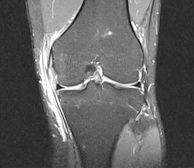

1. 분야별 전문 과장의 특성화 진료 좋은삼선병원 인공관절센터는 고관절, 무릎 관절, 어깨 관절, 수족부 관절 등 질환 부위별 특성화 진료를 통해 맞춤 치료를 시행합니다.

2. 인공관절시술 시행 병원(고관절 / 슬관절 / 견관절)좋은삼선병원 인공관절센터는 고관절, 슬관절, 견관절 등 다양한 인공관절시술을 시행하고 있습니다.